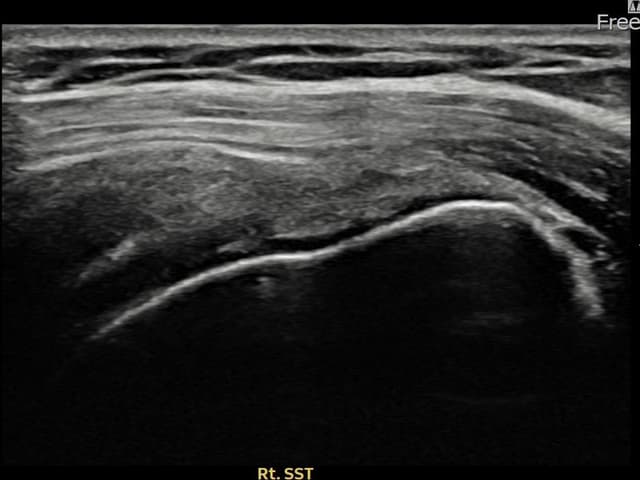

[촬영시기:23.09.01~23.11.03]

[어깨인대 축소봉합술] 우측 어깨 통증이 수개월간 지속되어 내원하셨습니다.